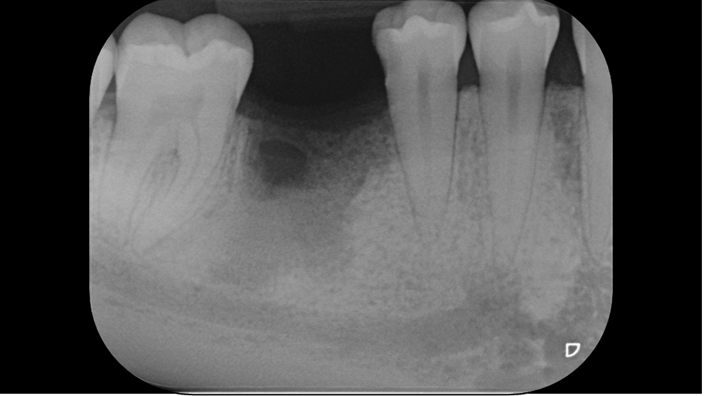

Clinical case: Ridge splitting technique using SmarThor + AnyRidge as expander

- Courtesy of Dr.Kwang-Bum Park, Korea -

AnyRidge, ridge splitting, GBR, Dr. Kwang-Bum Park, mandibular posterior, SmartThor, Mega-Oss, thin ridge, bone regeneration